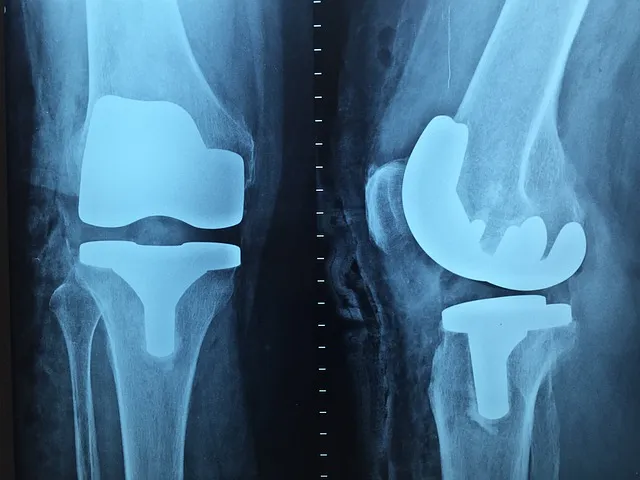

우리는 삶의 여정을 떠나면서 다양한 도전과 힘든 순간을 경험합니다. 그중에서도 관절과 연골 건강은 매우 중요합니다. 통증이 심할 때에는 영양제보다 치료가 우선되어야 합니다. 관절과 연골에 좋은 영양소에 대해 살펴보겠습니다. 알아보시고 건강관리에 도움이 되었으면 합니다.

글루코사민과 콘드로이틴은 연골 형성에 도움을 주는 핵심 성분입니다. 영양소는 관절 건강을 유지하는 데뿐만 아니라 퇴화를 예방하는 데에도 효과적일 수 있다고 연구에 따르면 밝혀졌습니다.

칼슘, 마그네슘, 비타민 D는 뼈와 관절을 지지하고 강화하는 데 중요합니다. 뼈와 관절의 건강은 우리가 일상생활에서 자유롭게 움직이고 활동할 수 있는 능력에 직접적으로 영향을 미칩니다.